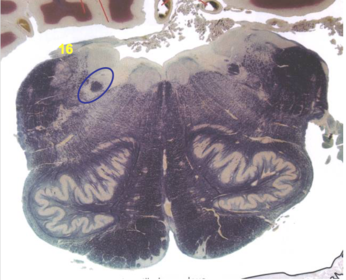

| Longitudinal pontine fibers (corticospinal tract) | |

| Transverse pontine fibers (dark fibers) | |

| Pontine nuclei (pale) | |

| Medial lemniscus | |

| ALS | |

| Trapezoid body | |

| Ventral trigeminothalamic tract | |

| Superior olive | |

| Central tegmental tract | |

| Facial nerve root fibers - descending | |

| Facial motor nucleus | |

| Interposed nuclei | |

| Medial longitudinal fasciculus | |

| Facial nerve root - internal genu | |

| Abducens nucleus | |

| Lateral vestibular nucleus | |

| Superior vestibular nucleus | |

| Inferior cerebellar peduncle | |

| Superior cerebellar peduncle | |

| Dentate nucleus | |

| Fastigial nucleus | |

| Anterior spinocerebellar tract | |

| Spinal nucleus of V | |

| Spinal tract of V | |

| Middle cerebellar peduncle | |

| Principle nucleus of V | |

| Mesencephalic V tract | |

| Trigeminal root fibers | |

| Motor nucleus of V | |